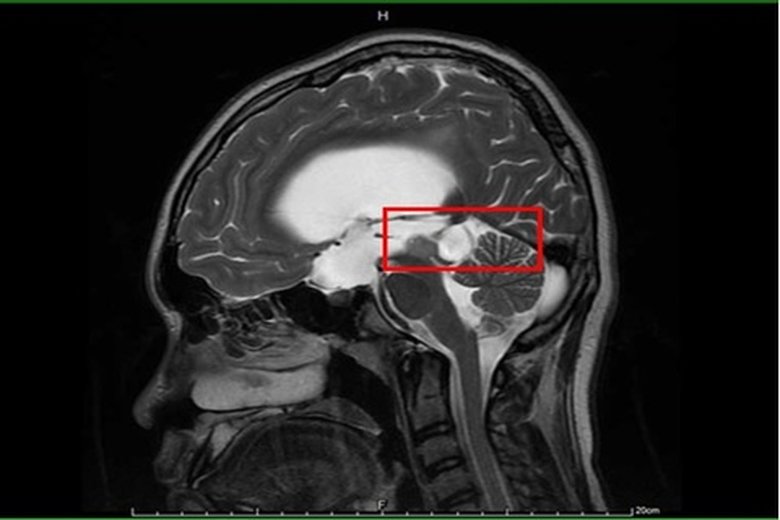

【新唐人亞太台 2020 年 09 月 23 日訊】15歲男孩因頭痛不適昏倒,被家人緊急送醫,經急診診斷疑為水腦合併癲癇,施以抗癲癇藥物治療。但男孩父母對癲癇病情仍有疑慮,故帶至臺大醫院新竹分院小兒神經科門診就醫。透過檢查,發現男孩眼動受限,眼睛無法往上看及往外側注視,醫師問診發現,他自小學四年級就開始頭痛,且因眼動受限而時常跌倒。經腦部核磁共振檢查確診為水腦併中腦腫瘤,立即安排手術治療。